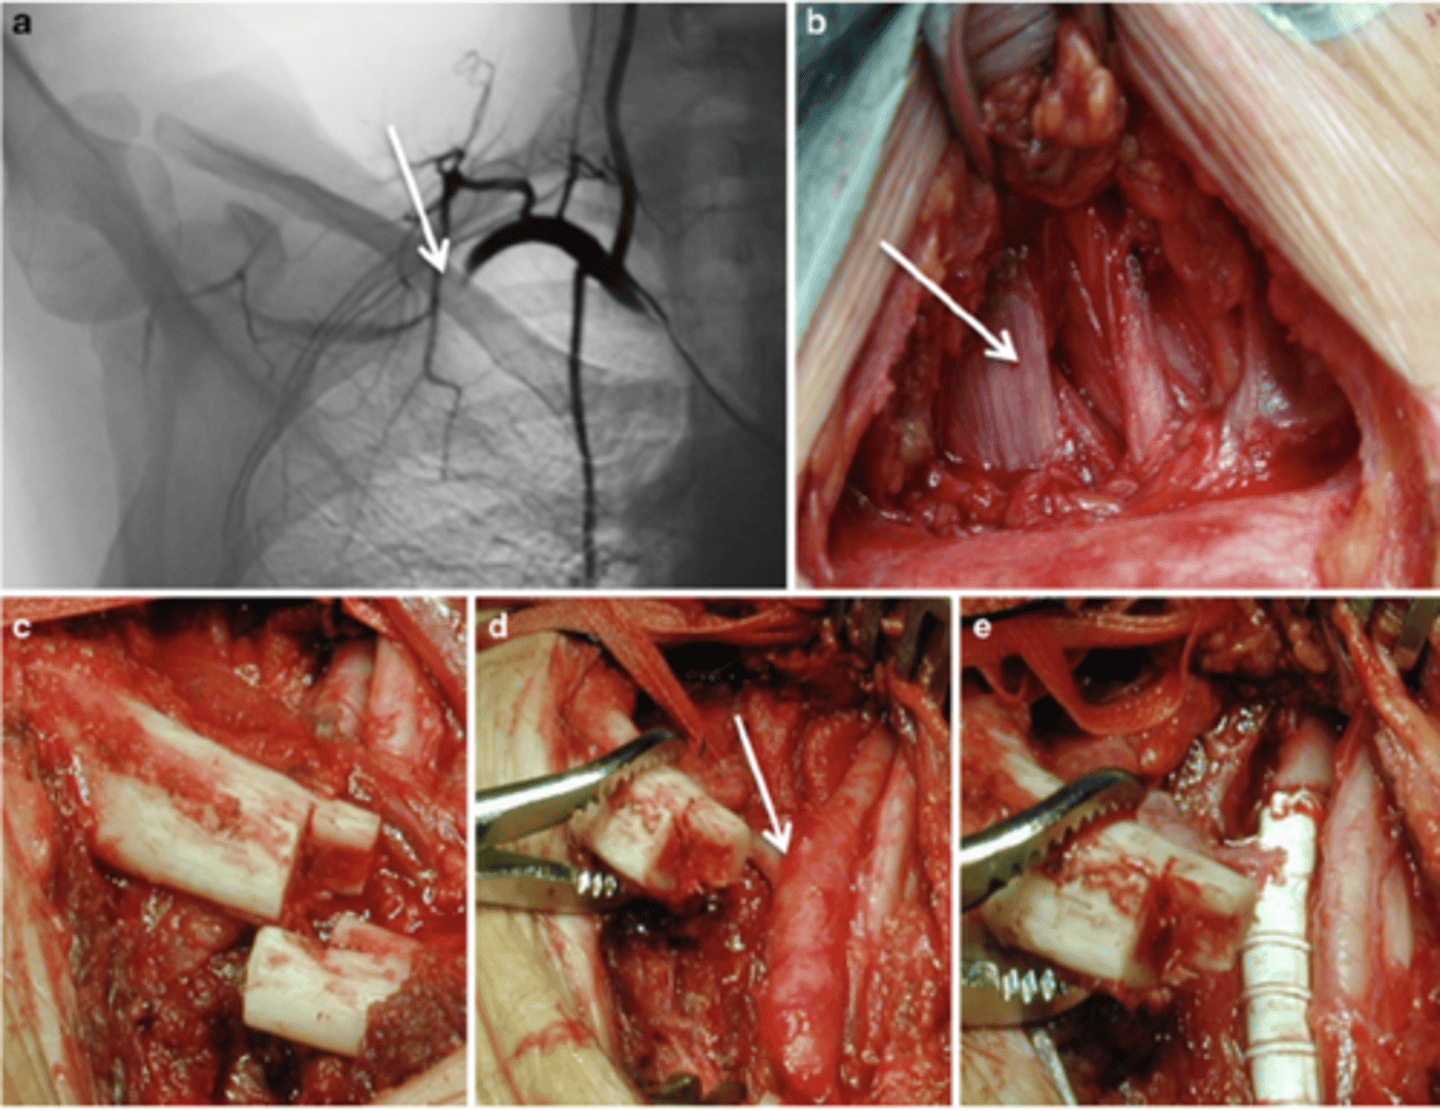

Symptoms persisting after 6 months of conservative treatment, progressive muscle atrophy, worsening neurologic deficits, or vascular TOS.

List three common surgical procedures for TOS.

Cervical rib resection, anterior or middle scalenectomy, and neurolysis (C7, C8, or T1).

embolic events, stenosis with persistent pain and vascular insufficiency, subclavian aneurysm, thrombosis with ischenia

What are the primary interventions for vascular TOS with critical ischemia?

IV heparin, embolectomy, local thrombectomy, endovascular stent placement, or vascular bypass/grafting.